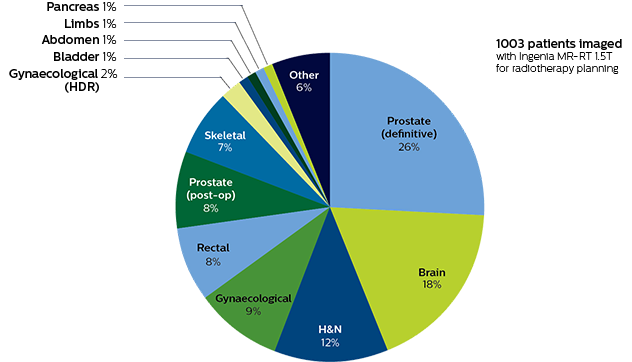

Distribution of patients undergoing MRI for treatment planning at TYKS

January 2016 - October 2017

The radiation therapy department at Turku University Hospital (TYKS) has been home to a Philips Ingenia MR-RT 1.5T since January 2016. This Ingenia is a workhorse for the department, as about 60% of the MRI scans performed are to aid in planning the hospital’s 1,600 radiotherapy patients per year, with cardiac and emergency diagnostic scans making up the balance. Approximately one in five of the radiotherapy cases are prostate cancer patients and for those, MRI simulation is part of the standard clinical care.

Distribution of patients undergoing MRI for treatment planning at TYKS

January 2016 - October 2017